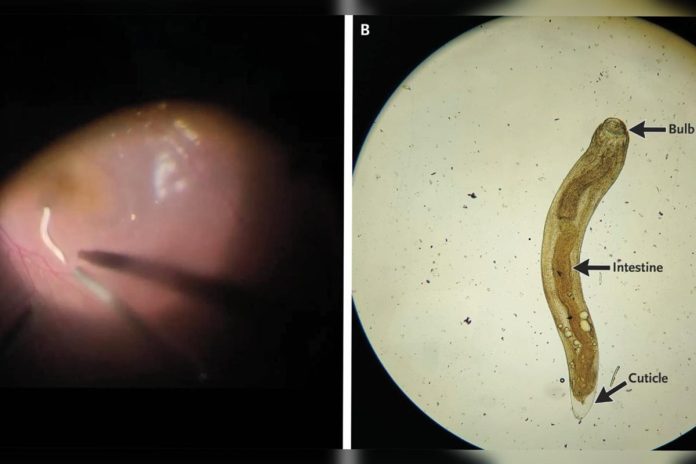

O globo ocular estava avermelhado, a pupila dilatada e fixa, e a precisão visual havia caído para 20/80. Durante o exame detalhado, os médicos identificaram o parasita se movendo no chamado “segmento posterior” — a parte interna e mais profunda do olho.

Para salvar a visão do paciente, foi realizada uma cirurgia chamada vitrectomia pars plana, que retira o humor vítreo (substância gelatinosa dentro do olho) e permitiu a retirada do verme.